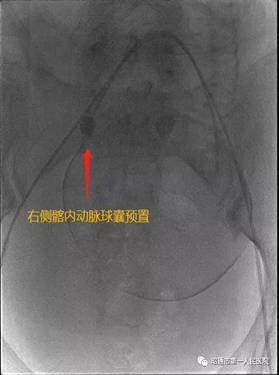

近日我院产科收治了一名由县级医院转入的孕妇。该孕妇年龄33岁,孕期多次B超提示:中央性前置胎盘伴植入可能。孕妇于2012年在其他医院行剖宫产术,2017年因瘢痕妊娠在云大医院行介入下手术。该孕妇入院后科室手术团队反复在科内B超下评估,结合她的病史及辅助资料考虑该患者胎盘植入的可能性很大,病情危急,决定术前邀请请普三科主任赵雄会诊。经会诊后拟术前行双侧髂内动脉球囊导管临时置入术。

术中见子宫下段血管丰富,怒张明显,胎盘广泛植入于子宫下段,伴穿透。如果按传统的胎盘打洞开窗取胎手术,孕妇可能瞬间大出血,危及生命。产科主任曹华及团队医师临时应变,经讨论决定借鉴省内外处理凶险性前置胎盘成功的经验,大胆探索子宫双切口术式,在接近宫底部取第一切口娩出胎儿后,由普三科手术团队行双侧髂内球囊临时阻断,子宫切口出血立即减少,剥离子宫切口周围胎盘组织,关闭第一切口。下推膀胱于子宫下段取第二切口,手剥胎盘,关闭第二切口。